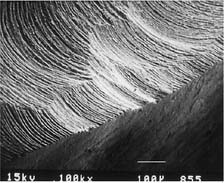

Table 7-3 MARGINS PRODUCED BY VARIOUS TYPES OF BURS

| Bur appearance | Low magnification of the prepared margin | High magnification of the prepared margin |

|---|---|---|

| CHAMFERS | ||

| Chamfer carbide (high speed) | ||

![]() |

| Finishing carbide (high speed) | ||

| Finishing carbide (low speed) | ||

| Chamfer diamond coarse (high speed) | ||

| Fine diamond (high speed) | ||

| Chamfer diamond fine (low speed) | ||

| SHOULDERS | ||

| Cross-cut fissure (high speed) | ||

| Cross-cut fissure (high speed) and hoe | ||

| Cross-cut fissure carbide (high speed) | ||

| Flat-end coarse diamond (high speed) | ||

| Flat-end coarse diamond (high speed) and hoe | ||

| Fine grit diamond (high speed) | ||

| Fine grit diamond (low speed) | ||

Courtesy of Dr. H. Lin.